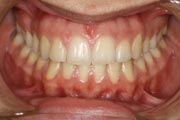

Crowding

Before